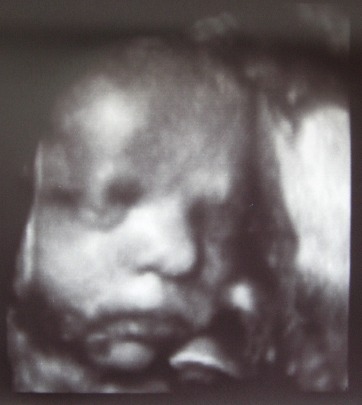

Наконец-то была на узи в арт-меде!!! Вот наш Илюшка! Мы на узи сосали большой палец, играли с пуповиной и пробовали ее на вкус, показывали родителям язык:))) Весим мы уже 2 кг 300 гр